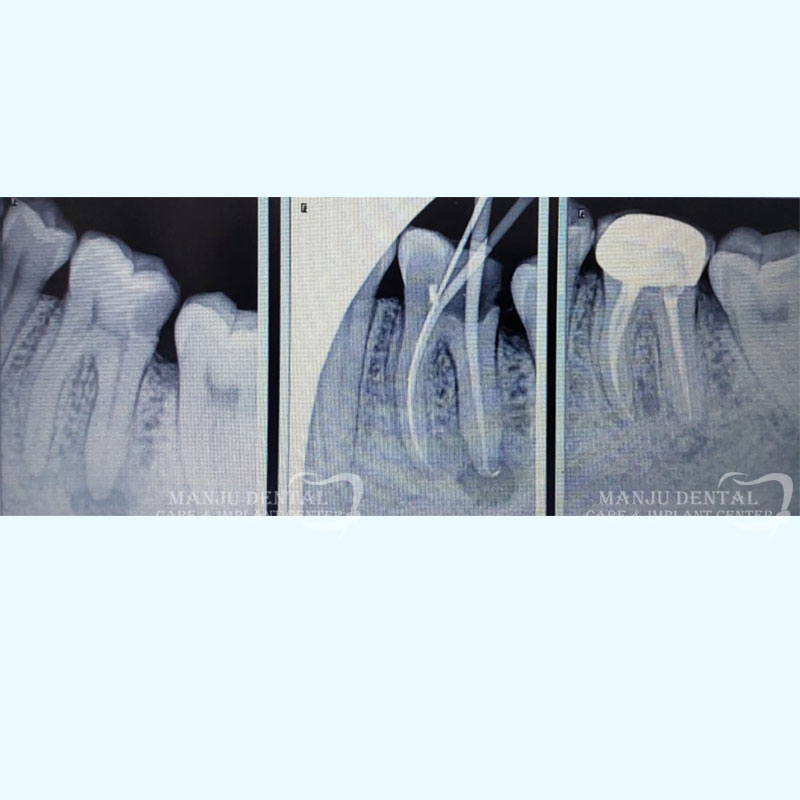

Nonsurgical Management of Large Periapical Lesion

1.  After clinically examining the tooth, a radiograph is done using x-rays and  local anaesthesia is administered to make tooth numb. An assess opening is done to enter pulp chamber and very small instruments are used to clean the pulp from the chamber and root canals of the tooth.

2. After the space is cleaned and shaped, the root canals are filled with a biocompatible material called gutta-percha. The gutta-percha is placed with a endodontic sealer to ensure complete 3D obturation of the root canal system. After obturation a permanent restoration is done to completely seal the tooth.

3. After the final visit a crown or other restoration is placed on the tooth to protect and restore it to full function.